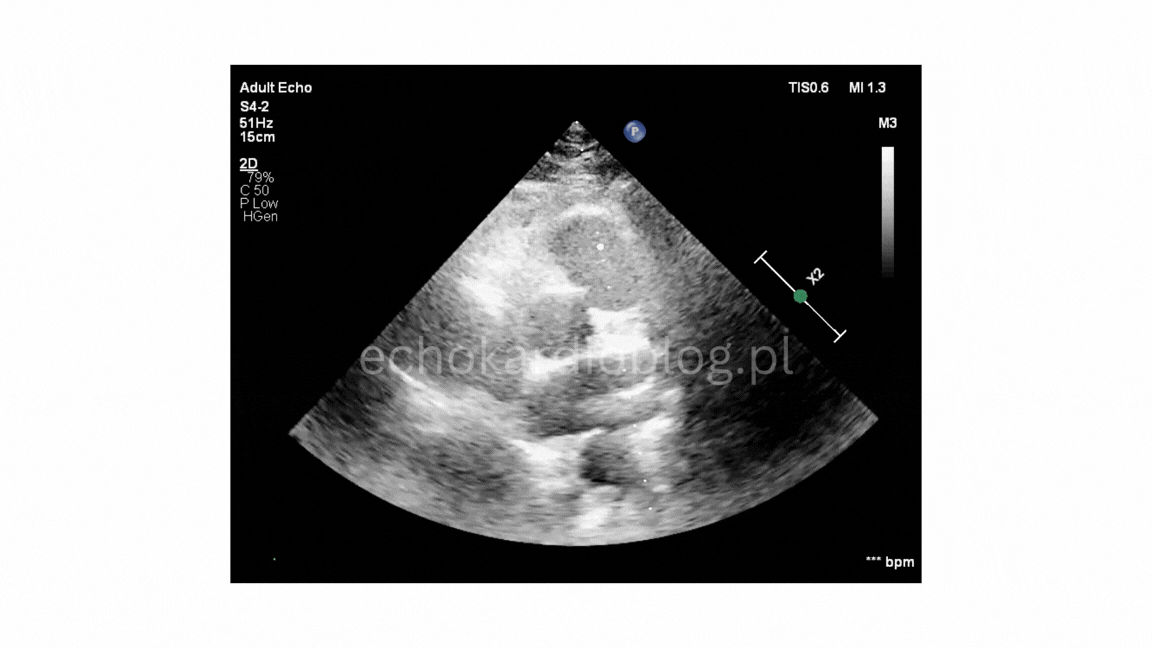

Przypadek 3.B

W trzecim – warunki obrazowania są trudne i nawet przy podejrzeniu BAV potwierdzenie diagnozy może być niepewne.

In the third, imaging conditions are very challenging, and even if BAV is suspected, confirmation may be uncertain.

Takie zestawienie pokazuje, że znajomość cech BAV musi iść w parze z umiejętnością oceny jakości obrazu i świadomością jego ograniczeń

This comparison demonstrates that recognizing BAV depends not only knowing its typical features but also on the ability to assess image quality and understand its limitations.